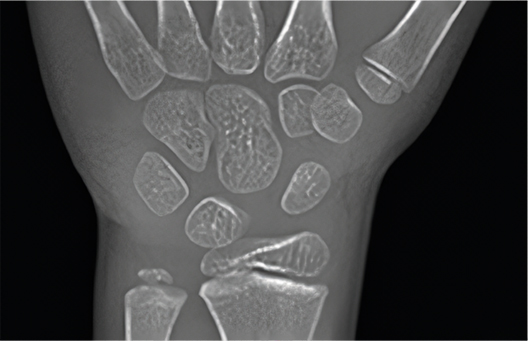

• Closed Growth Plate